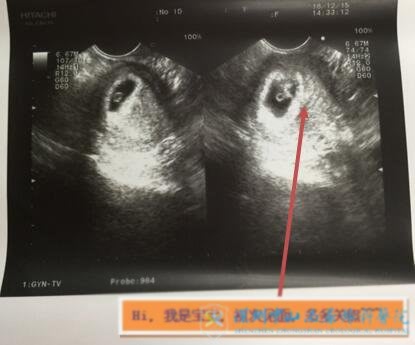

2018年9月,罗女士新鲜移植了1枚囊胚,没有着床。但在张医生的鼓励下,罗女士依然充满信心。11月份,在进行了宫腔镜的排查后,罗女士进行了第二次胚胎移植,12月15日B超提示:宫内妊娠!